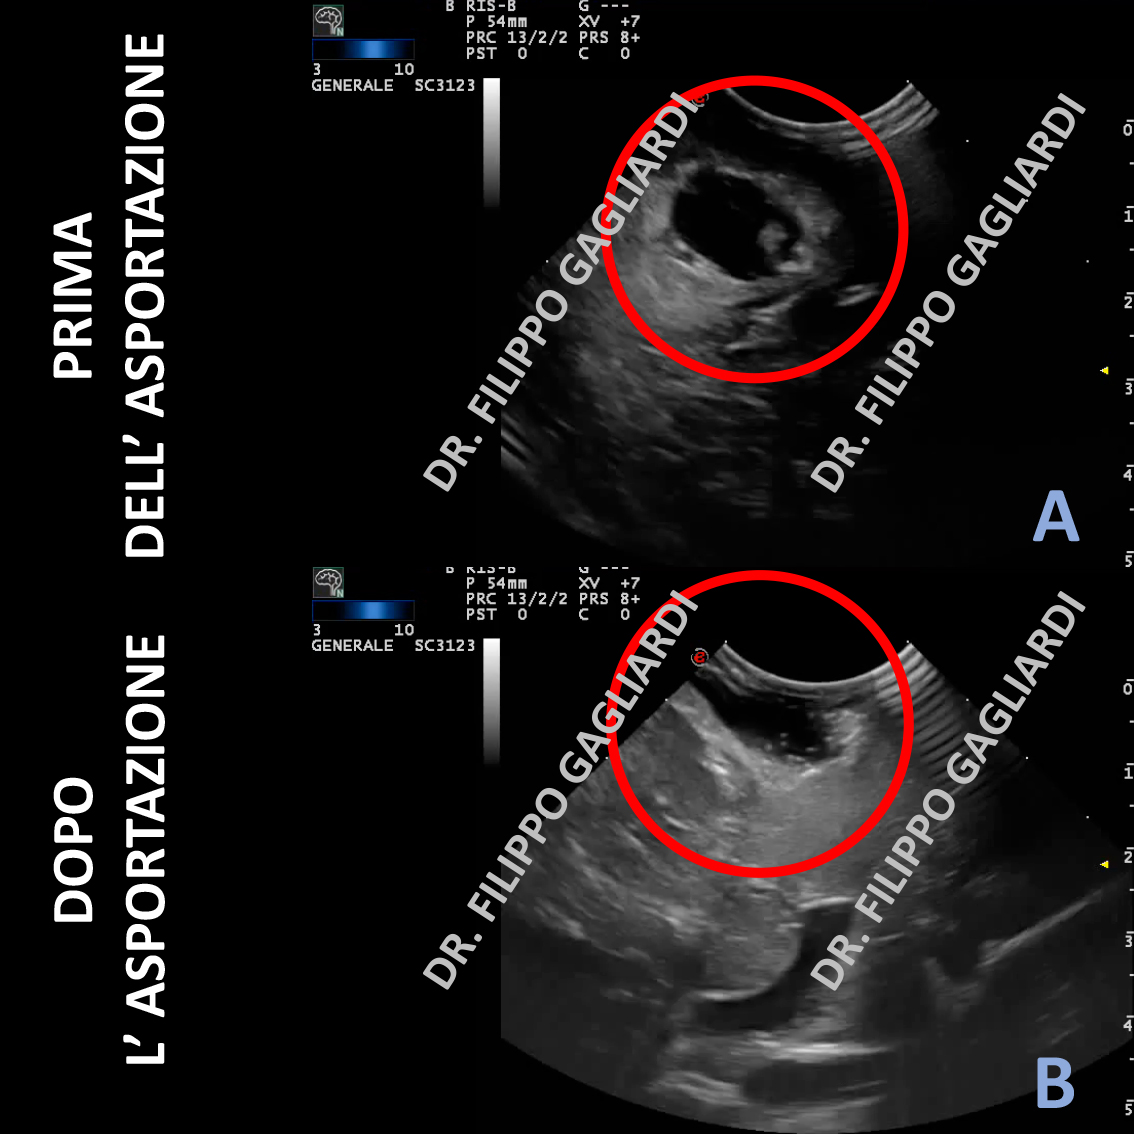

La foto rappresenta la scansione ecografica prima (Figura A) e dopo (Figura B) l’asportazione di un tumore al cervello (cerchio rosso).